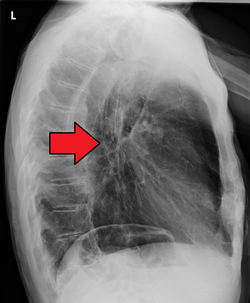

If the cancer has spread elsewhere, symptoms related to metastatic disease may appear. Common sites of spread include nearby lymph nodes, the liver, lungs and bone.[14] Liver metastasis can cause jaundice and abdominal swelling (ascites). Lung metastasis can cause, among other symptoms, impaired breathing due to excess fluid around the lungs (pleural effusion), and dyspnea (the feelings often associated with impaired breathing).

Additional testing is needed to assess how much the cancer has spread (see § Staging, below). Computed tomography (CT) of the chest, abdomen and pelvis can evaluate whether the cancer has spread to adjacent tissues or distant organs (especially liver and lymph nodes). The sensitivity of a CT scan is limited by its ability to detect masses (e.g. enlarged lymph nodes or involved organs) generally larger than 1 cm.[43][44] Positron emission tomography is also used to estimate the extent of the disease and is regarded as more precise than CT alone.[45] PET/MR as a novel modality has shown promising results in preoperative staging with fair feasibility and good correlation in comparison to PET/CT. It can enhance tissue differentiation with lowering the radiation dose to the patient.[46] Esophageal endoscopic ultrasound can provide staging information regarding the level of tumor invasion, and possible spread to regional lymph nodes.